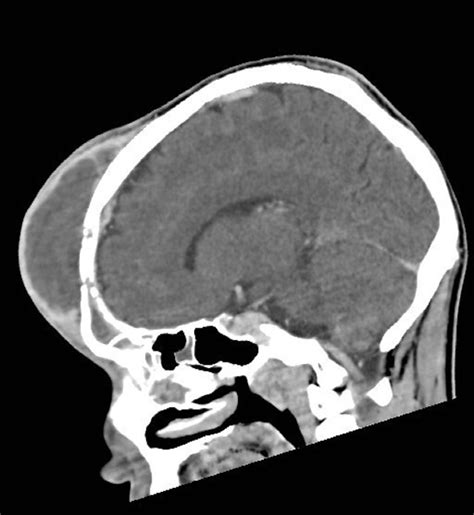

At its core, Pott's Puffy Tumour is not a true neoplasm or tumor in the oncological sense, but rather a clinical presentation of an osteomyelitis of the frontal bone. It is almost always secondary to untreated or inadequately treated frontal sinusitis or direct trauma to the forehead. The infection spreads from the frontal sinus into the marrow space of the frontal bone, creating a localized collection of pus—an abscess—beneath the periosteum. This causes the classic "puffy" appearance on the patient's forehead.

The progression of the condition can be rapid. Because the bone is porous, the infection can easily penetrate the inner table of the skull, leading to an intracranial abscess or meningitis. Understanding this mechanism is crucial because the superficial swelling is often just the "tip of the iceberg" regarding the extent of the infection inside the cranium.

Diagnosis of Pott's Puffy Tumour relies heavily on advanced medical imaging. Physical examination is insufficient to determine the depth of the bone involvement or the presence of intracranial complications. Radiologists and surgeons work in tandem to evaluate the extent of the disease.

Computed Tomography (CT) To visualize bone erosion, sinus opacification, and subperiosteal abscess.